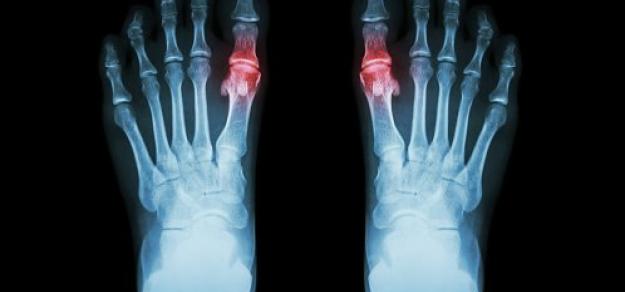

En pacientes con gota y sin enfermedad coronaria, el uso prolongado de alopurinol protege contra el primer síndrome coronario agudo (SCA) en comparación con los no usuarios. Por el contrario, los iniciadores del alopurinol, que posiblemente tenían más inflamación sistémica, tenían un mayor riesgo de SCA por primera vez en comparación con los usuarios a largo plazo. BMJ Open, 27 de febrero de 2025